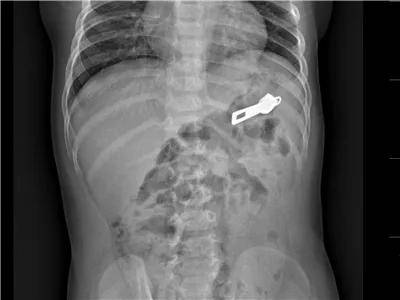

1岁·拉链头

入院1小时前误服拉链头,约12mm大小。